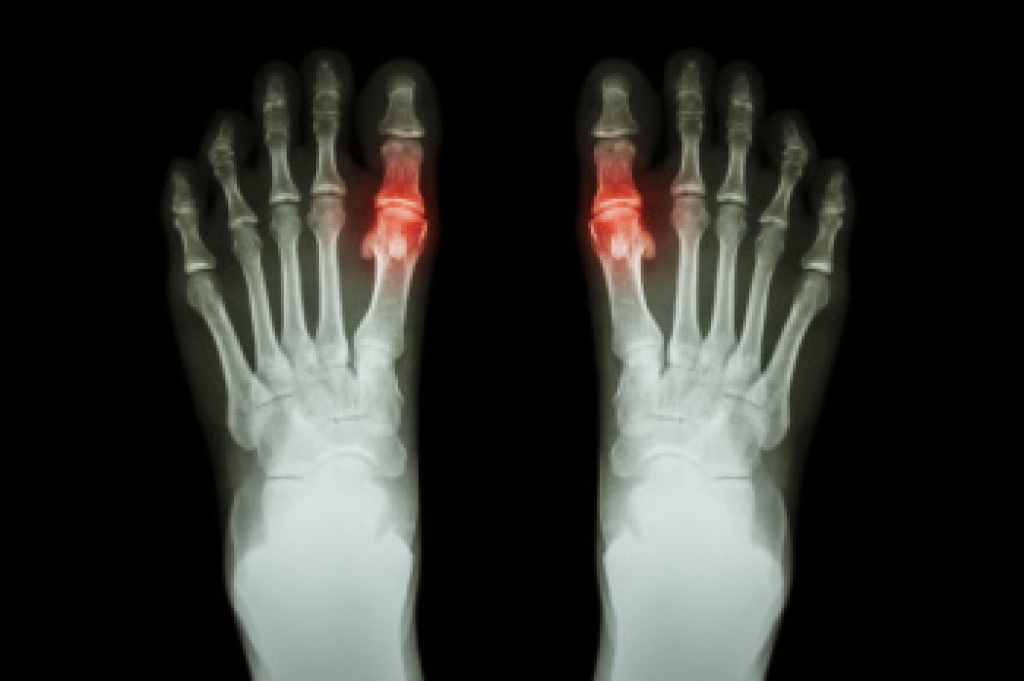

Gout is a type of arthritis caused by the buildup of uric acid crystals in the joints, often affecting the big toe. It occurs when the body produces too much uric acid or does not excrete enough through urine. Symptoms include sudden, intense pain, redness, swelling, and warmth in the affected joint, typically during the night. Gout attacks can feel excruciating, making even the lightest touch unbearable. Treatment for gout involves medications like nonsteroidal anti-inflammatory drugs called NSAIDs, colchicine, or corticosteroids to reduce pain and inflammation. Long-term management may include medications to lower uric acid levels and lifestyle changes like reducing alcohol intake and eating a purine-free diet. A podiatrist can help diagnose gout, manage flare-ups, and provide advice on footwear and exercises to reduce strain on affected joints. If you are experiencing symptoms of gout, it is suggested that you schedle an appointment with a podiatrist for effective treatment and management.

Gout is a type of arthritis caused by a buildup of uric acid in the bloodstream. It often develops in the foot, especially the big toe area, although it can manifest in other parts of the body as well. Gout can make walking and standing very painful and is especially common in diabetics and the obese.

Gout can easily be identified by redness and inflammation of the big toe and the surrounding areas of the foot. Other symptoms include extreme fatigue, joint pain, and running high fevers. Sometimes corticosteroid drugs can be prescribed to treat gout, but the best way to combat this disease is to get more exercise and eat a better diet.